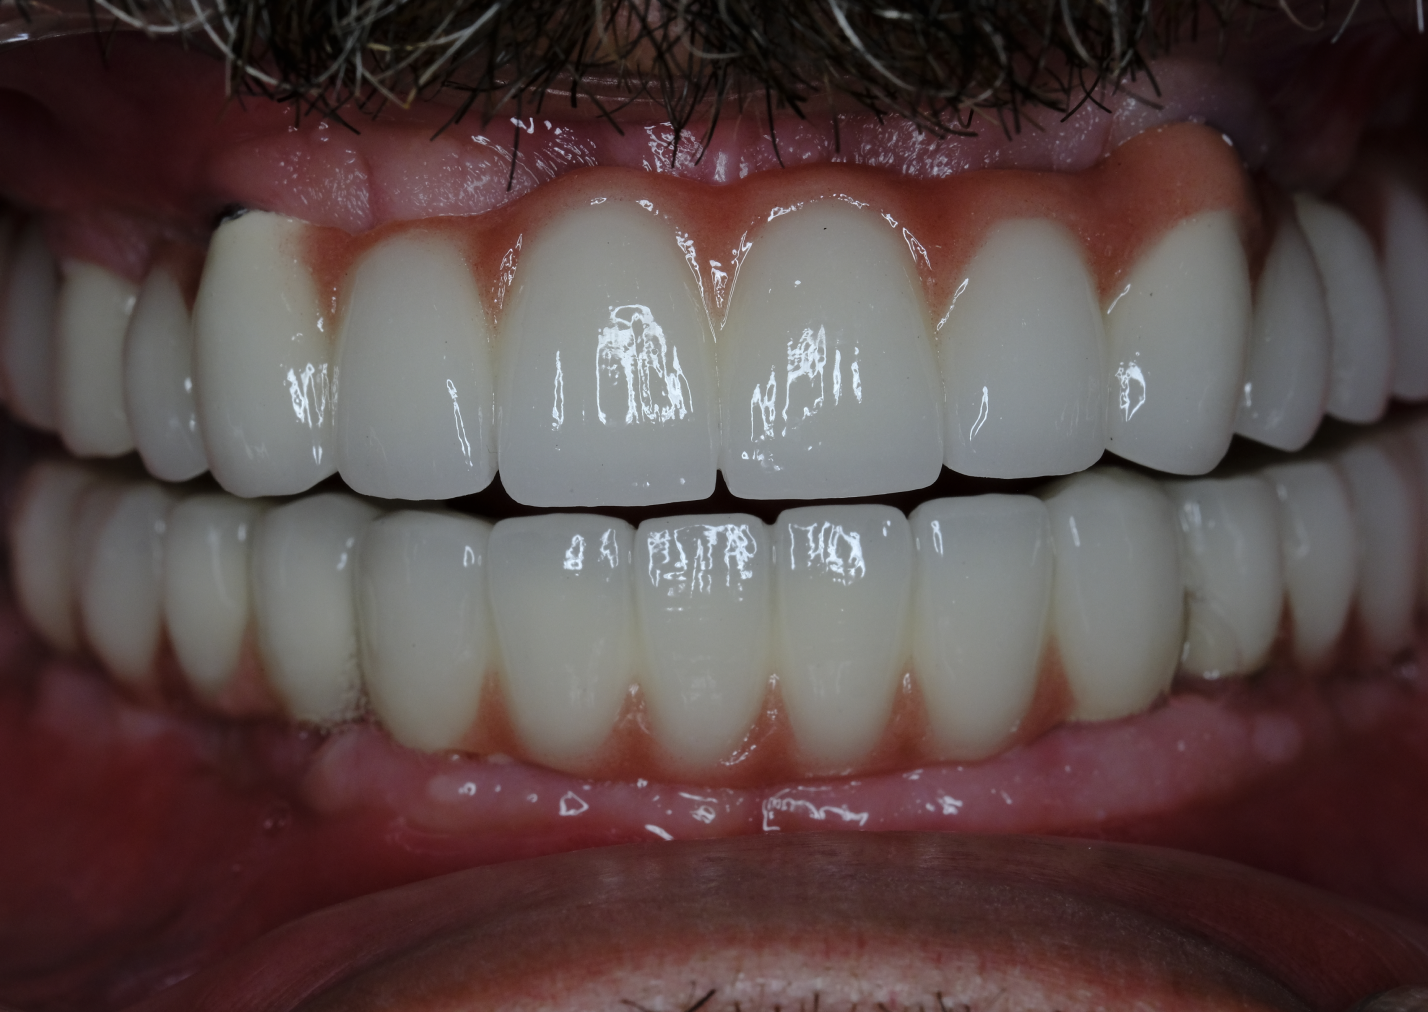

Sinus Avoidance Technique: Placement of 4 Upper Jaw and 6 Lower Jaw Implants

In cases where sinus augmentation procedures are not feasible or preferred, alternative techniques must be employed to ensure successful implant placement in the upper jaw. This case presentation discusses the utilization of a sinus avoidance technique for the placement of 4 implants in the upper jaw and 6 implants in…